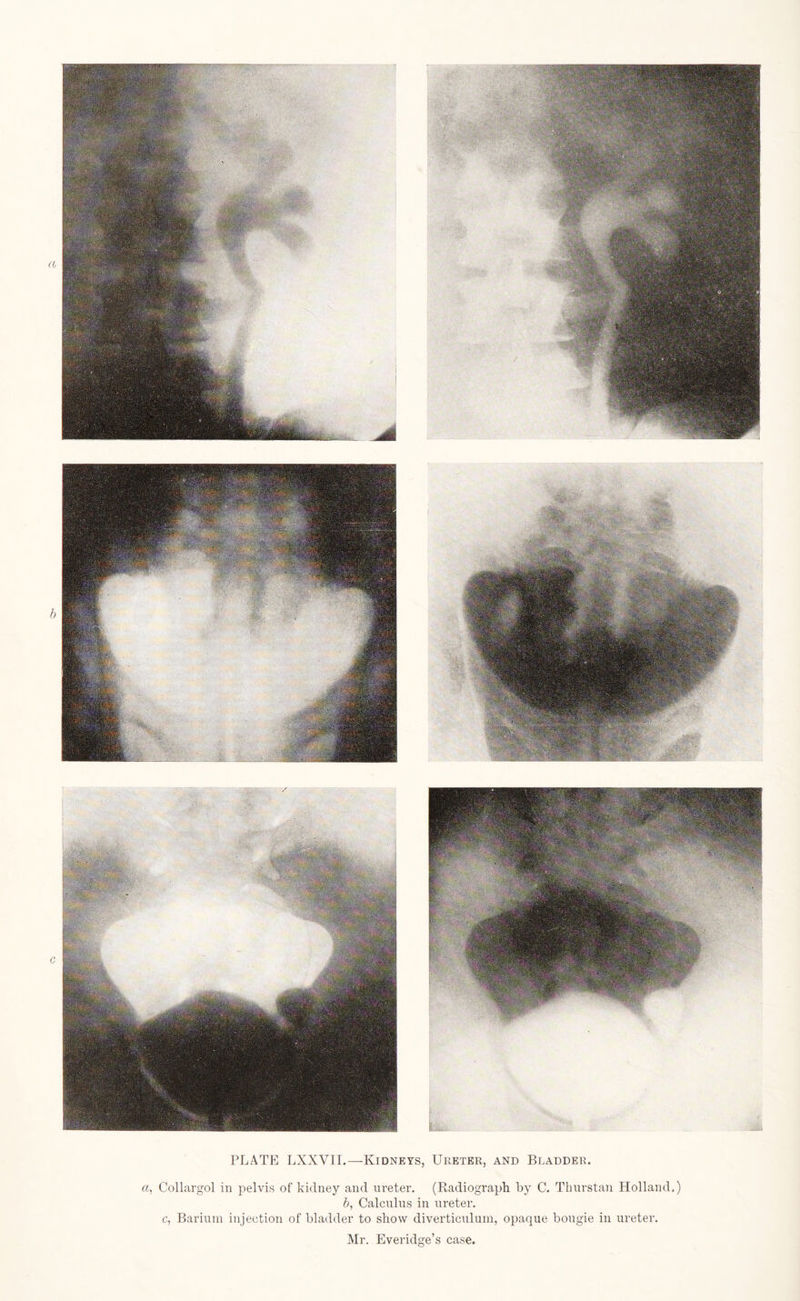

Radiography and radio-therapeutics / by Robert Knox.

Credit: Radiography and radio-therapeutics / by Robert Knox. Source: Wellcome Collection.